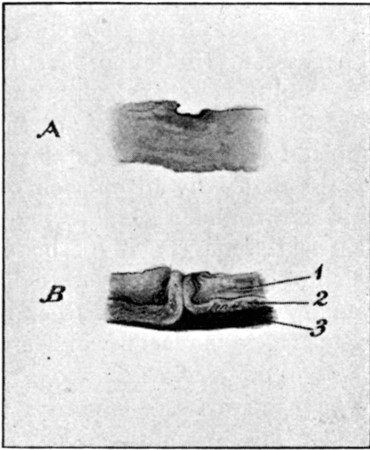

1. Section of Mauser Aperture of Entry To face p. 73

2. Section of Mauser Aperture of Exit 76

25a. Sections of Mauser Entry and Exit Wounds74